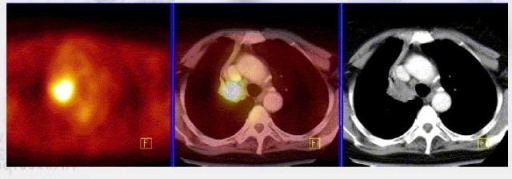

Jedinečnost kombinovaného PET/CT vyšetření

spočívá ve spojení funkčních a anatomických informací. Pomocí

počítače lze provést fúzi obrazů z obou modalit (PET i CT) a lze

přesně určit, ve které anatomické struktuře se nachází patologické

ložisko se zvýšenou metabolickou aktivitou.